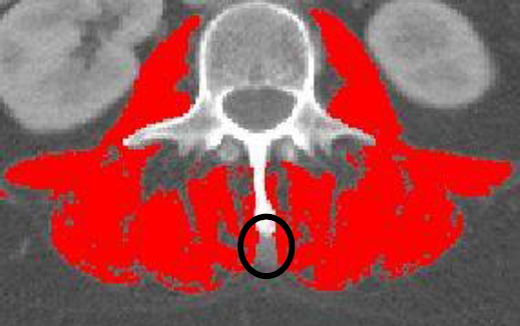

·For skeletal muscle analysis, all muscles at the L3 region will be analyzed (TAG 1- Red, HU Range: -29 to +150)

·The area underneath the vertebrae should remain untagged

·If the neural spine is present in the L3, the area underneath the neural spine should remain untagged